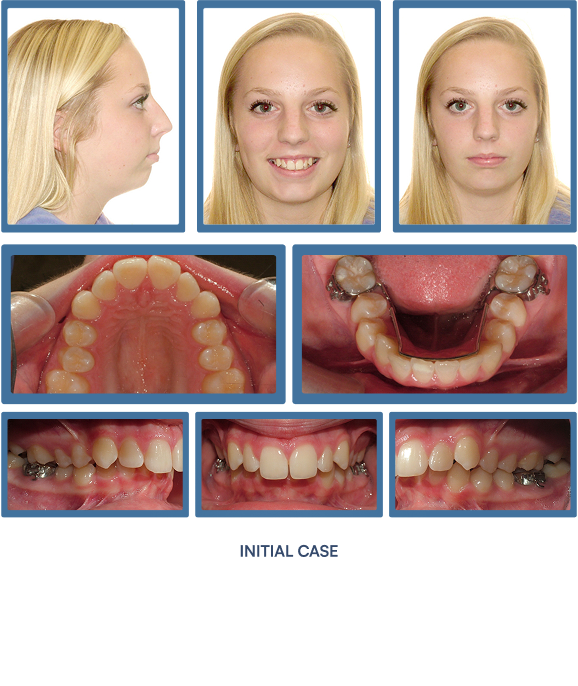

Orthodontic treatment does more than align teeth—it strategically improves the structural support of the lips and lower face. As teeth and jaws are brought into optimal alignment with braces or Invisalign®, many patients experience visibly fuller, more defined lips and an enhanced facial profile. These subtle yet impactful changes contribute to a more youthful, harmonious appearance—making orthodontics a powerful tool not only for oral health, but for facial aesthetics.